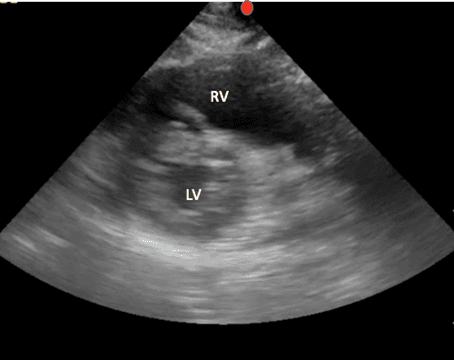

This view allows for evaluation of the left ventricle function, symmetry of squeeze and septal bowing. The left ventricle can be identified in this view and appears as a circular at the bottom right of the screen. The right ventricle appears crescent shaped and is located in the upper right part of the screen (Image 7).

PSS Labeled Structures

Fanning the probe too apically and viewing the apex of the heart rather than the papillary muscles (Image 8) will give you an incorrect assessment of left ventricular function.

Splint image PSS at Papillary Muscles and Apex

* Papillary Muscle View

Apical PSS view